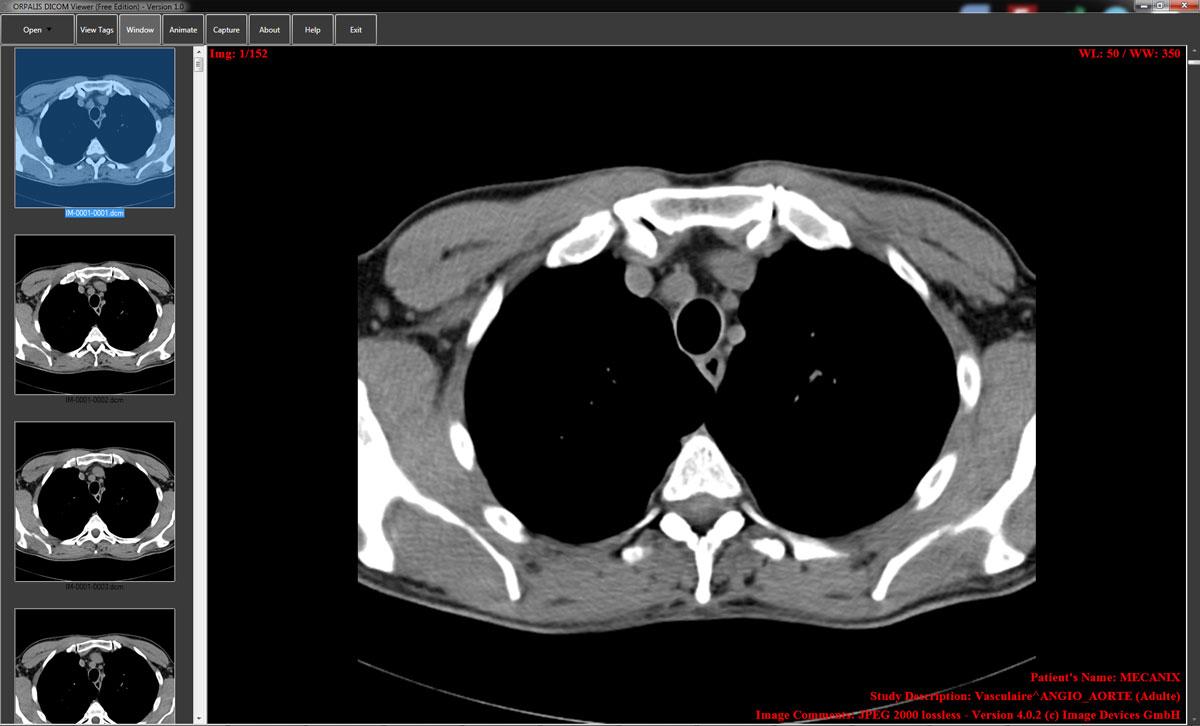

Modern medical diagnosis and treatment planning presuppose the application of digital imaging. Scans must be read accurately to enable clinicians to interpret the scan. DICOM standards bring uniformity to the imaging equipment and health systems.

Software should not degrade the image quality and metadata. Medical image viewer software provides clinicians with an opportunity to retrieve, analyze, and interpret DICOM data effectively. The inadequate visualization devices are likely to slow the diagnosis and pose a clinical risk.

DICOM viewers have more than simple image display functions. They understand embedded metadata and visual data. This is because window leveling assists in contrast optimization to diagnose properly. There is the zoom and pan functionality.

Multi-series and multi-frame navigation facilitates complicated research. Anatomical measurements are evaluated with the help of measurement tools. Clinical reporting is facilitated by the use of annotation features. There is the support of modality; it consists of CT, MRI, ultrasound, and X-ray.

Diagnostic reliability has a direct relationship with performance. The viewers are required to manipulate massive DICOM files in real-time. The accuracy rendering method maintains pixel accuracy and spatial resolution.

By providing high-bit-depth, the grayscale representation is correct. Image editing is enhanced by the use of a GPU. Form Hairs Consistency cross-platform compatible interfaces. Stability aids against crashing during important reviewing.

There is efficient caching, which enhances load times. Image reconstruction should not be unfaithful to the initial scans. Clinical interpretation is made possible through accurate visualization. The performance-oriented viewers increase trust and diagnostic consistency.